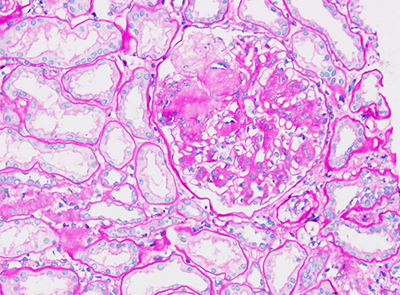

ÌṩͨÀýµÄʯÀ¯ÇÐÆ¬¡¢H&EȾɫÕï¶Ï£»£»£»

Ìṩ±ù¶³ÇÐÆ¬¡¢ÌØÊâȾɫ¡¢ÃâÒß×éÖ¯»¯Ñ§È¾É«¼°×éÖ¯½»Ö¯·´Ó¦£¨TCR£©µÈÕï¶ÏЧÀÍ£¬£¬£¬ £¬£¬Öª×ã¿Í»§¶ÔÌØ¶¨ÊÔÑéµÄ×éÖ¯ÊÓ²ìÐèÇ󡣡£¡£¡£¡£

• ÌØÊâȾɫ

ÌØÊâȾɫ-·¬ºì¹ÌÂÌȾɫ.jpgÌØÊâȾɫ-PASȾɫ.png